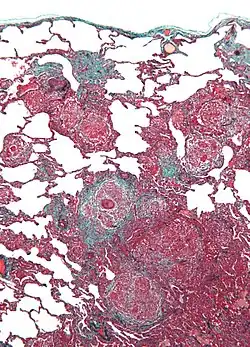

Histologisches Bild einer allergischen Lungenreaktion wie sie bei der Vogelhalterlunge typisch ist.

Bei den Allergenen, die diese Krankheit auslösen, handelt es sich um tierische Proteine, die im Staub und Kot von Vögeln auftreten. Federn in Daunen-Textilien kommen ebenfalls in Frage. Diese Allergene führen zu einer entzündlichen Reaktion des Lungengewebes, die durch eine Immunkomplexreaktion vom Typ III verursacht wird.